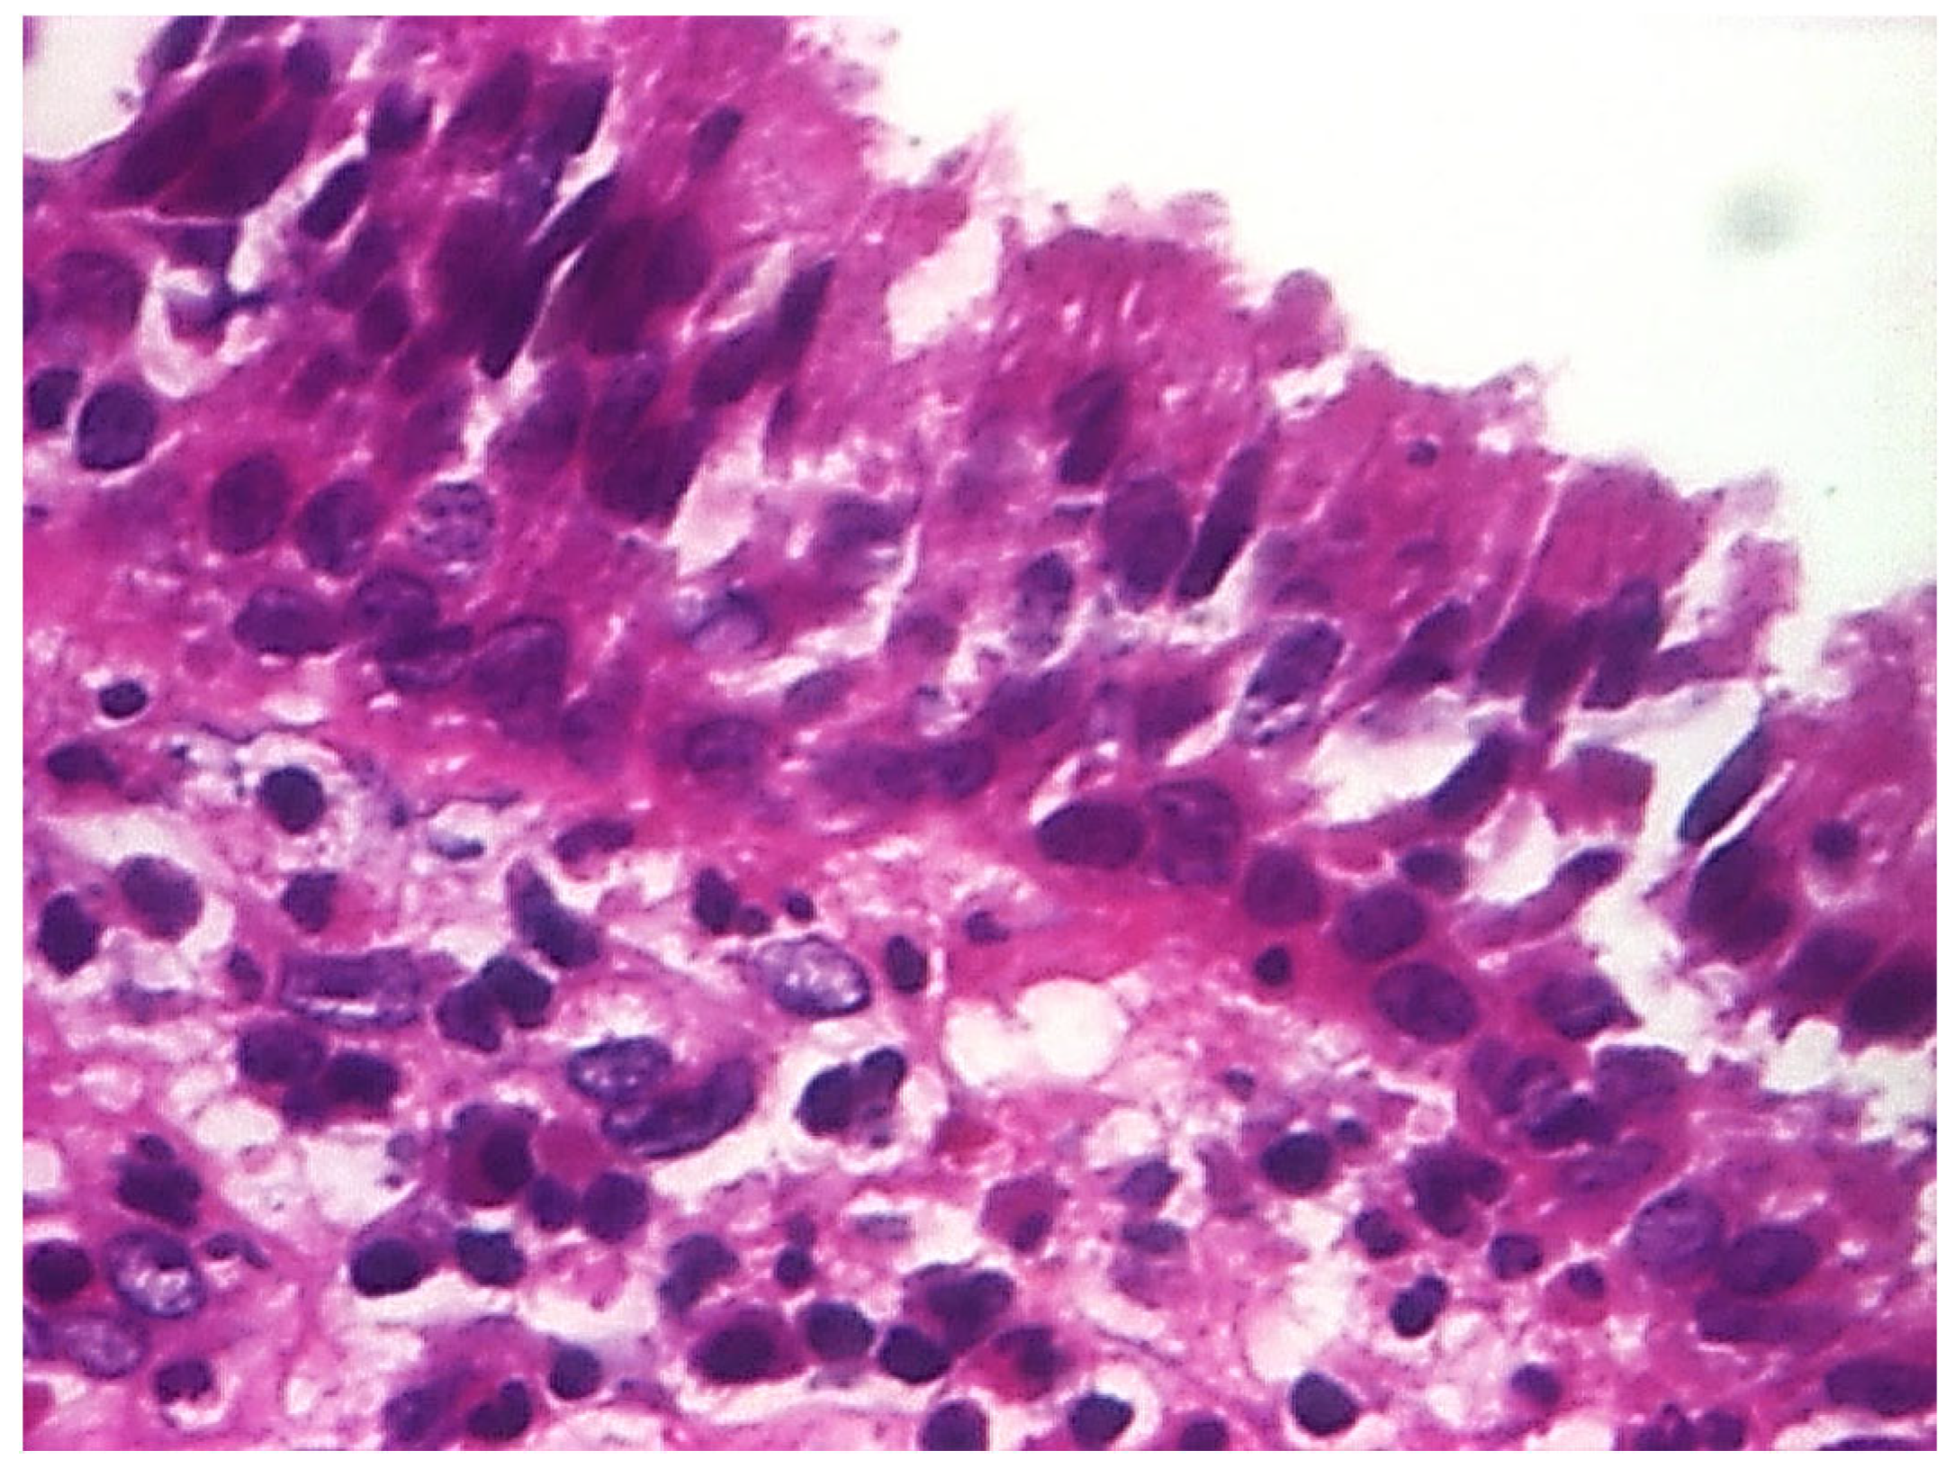

3.1.3. Analysis of Histopathologic and Immunohistochemical Results

| Tympanic membrane mucosa chamber, epithelium with apocrine-like cells, and chronic inflammatory infiltrate | 128 |

| Cell Types | Percentage |

|---|---|

| Lymphocytes T | 42.55% |

| Lymphocytes B | 31.45% |

| Macrophages | 26.00% |